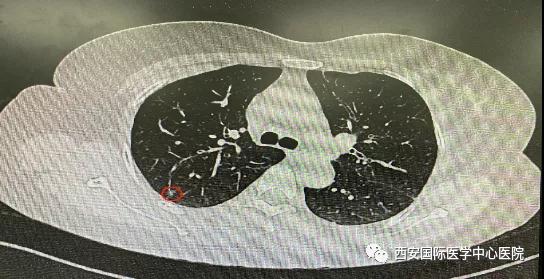

日前,西安國際醫學中心醫院胸科醫院胸外科二病區成功開展LungPro全肺導航下經支氣管鏡注入亞甲藍染色劑標記結節位置,行精準肺段切除術,成為西北地區首例“Lung Pro全肺診療導航系統聯合單孔胸腔鏡下右肺上葉后段切除術”,填補了西北地……